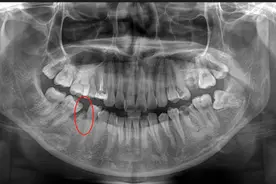

在临床操作中多人不会拍片,角度不对,整不明白,尤其是一些实习生。今天我给大家说说怎么快速学会拍牙片。首先拍片时牙位很重要。根据每一位病人的患牙部位,选择不同的拍摄角度。放胶片前先调好球头的角度部位- X倾斜方向- X管倾斜角度上1.2 向足侧倾斜 +42度上3 同上 同上上4.